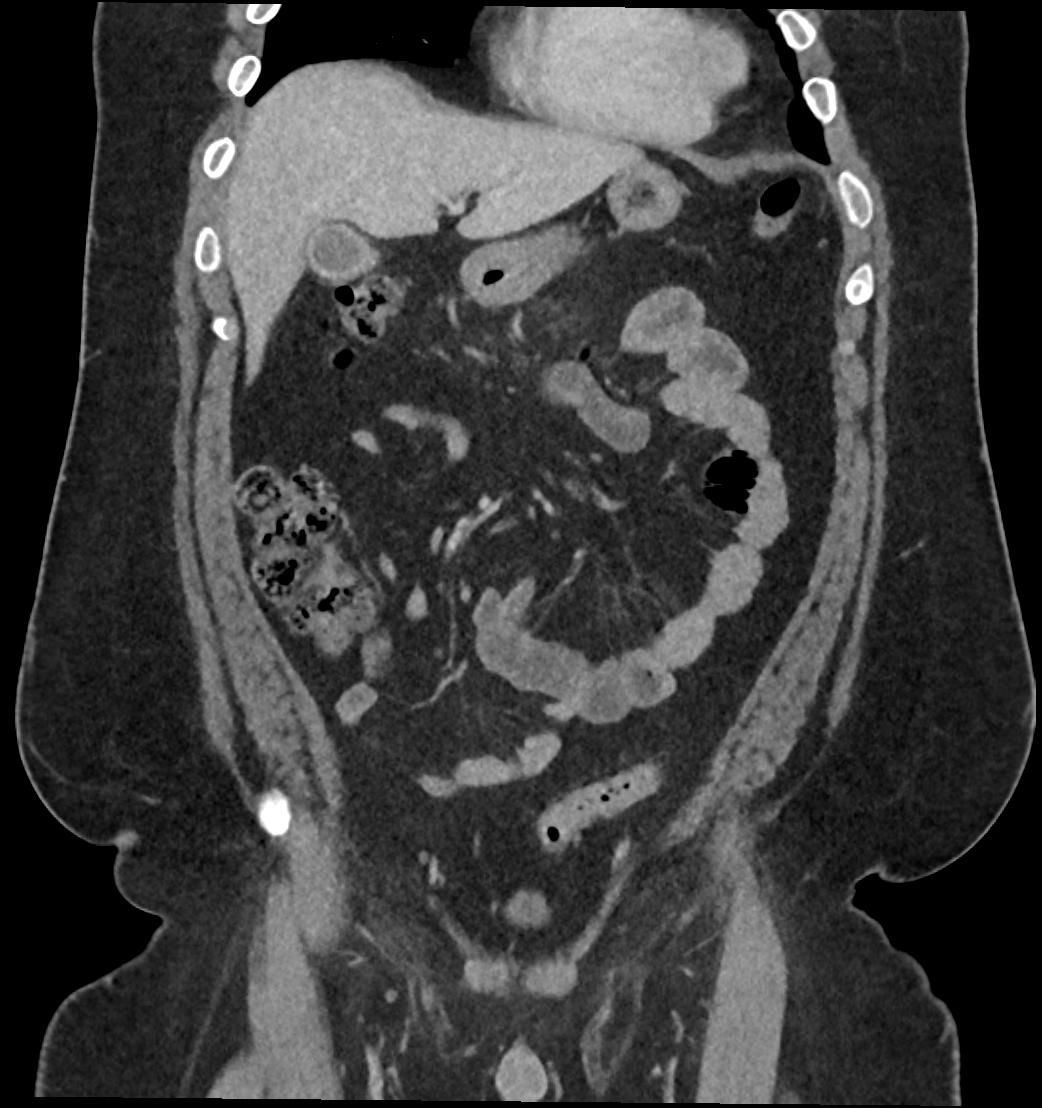

Patient: Padmakumar A. , *1988-04-24, PID: 3000069741773230809

Study Description: CT ABDOMEN

Image Series: Abdomen Cor 3mm [4]

<< Previous | Image 44 of 119 | Next >>